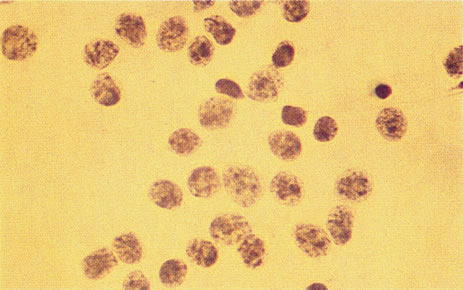

Figure 16 shows a case of what clinically and ultrasonographically appeared to be a uveal melanoma. The FNAB specimen revealed a cellular pattern that was diagnostic of a primary carcinoid (Fig. 17), and the patient responded dramatically with 40 gray of photon radiation. Figure 18 shows the FNAB cytopathology of a typical epithelioid choroidal melanoma; in contrast, a smear of a spindle cell tumor has spindle-shaped cytoplasm and smaller nuclei. Figure 19 shows a benign pigmented mass, such as a retinal pigment epithelial proliferation or a melanocytoma. In contrast to a melanoma, this type of mass has much larger pigment granules and benign cytomorphologic detail. In addition to standard cytopathologic FNAB evaluation, aspirated material may be used for several molecular biology studies (e.g., fluorescence in situ hybridization, comparative genomic hybridization), flow cytometry, special stains, tissue culture, and ultrastructural analyses.